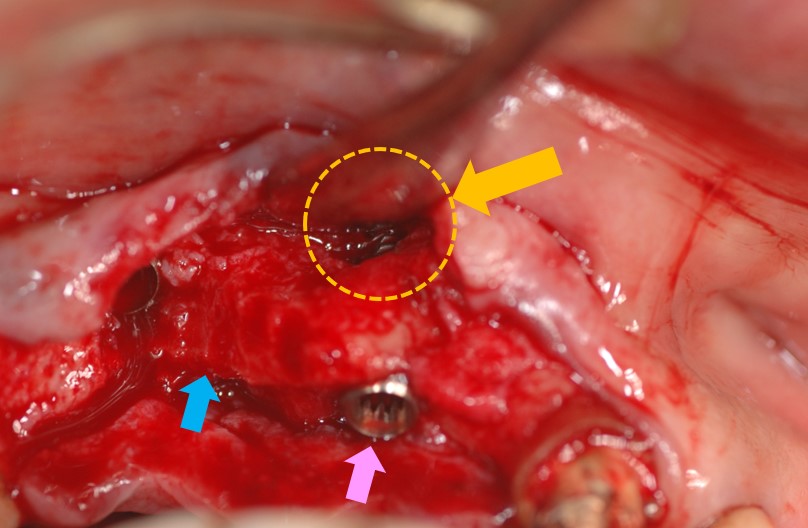

下写真はインプラント埋入手術を行っています。青矢印が「歯槽骨(骨)」で、その幅の中にインプラントを埋入しなければなりません。ピンク矢印がインプラントです。しかしながら、骨幅が足りなかったため、オレンジ矢印部分のインプラントが露出してしまいました。